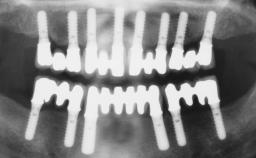

Immediate Loading of Six Implants in the Maxilla and Final Restoration with a Full-Arch Gold/Ceramic FDP Involving the Concept of Tilted Implants

A 61-year-old male patient with a failing fixed maxillary rehabilitation and a fixed mandibular rehabilitation requested a new fixed maxillary rehabilitation. The patient was wearing a temporary metal-reinforced maxillary bridge inserted two years before the consultation. He reported that his previous dentist did not want to insert a definitive framework because he considered the residual teeth to have a negative prognosis. The patient reported a history of recurrent caries and endodontic complications as the main reason for the previous extractions. The anamnesis was negative for periodontal disease and bruxism. The patient’s chief compliant was the mobility of his maxillary prosthesis, which needed to be re-cemented frequently, and discomfort during chewing.Moreover, the patient was not satisfied with the esthetic appearance of his maxillary teeth, which he found too long. The patient asked for a stable and comfortable fixed maxillary rehabilitation and firmly rejected any removable solution.